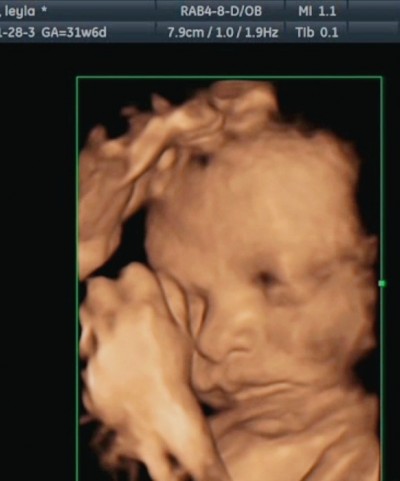

Kızlar selam. Ilk gebeliğim, doktordan geliyorum şimdi. Bebeğim iyi ama kordon dolanmış boynuna en çok korktugum şey doktor onemsemedi pek daha doğrusu doğal bi durum sorun yok dedi. Ama anne yüreği korktum biraz :( atkı giymiş gibi yavrum of of bu sefer ki ultrason resimlerine bakinca gözüm doluyo. :( Boynuna dikkatli bakın kac kere dolanmış filan hic bilmiyorum doktorum bi sey demedi. Çook hareketli bi bebek bununla alakalı olabilir mi? Doğumum benm bazı sağlık sorunlarımdan dolayı sezeryan olucak. Sizce doğuma kadar kordon çıkar mı? Benm yapabileceğim bi sey var mi? Varsa nedir? Tecrübeli annelerden fikir istiyorum.

Gebelik haftası 31+6

Alt dudagiyla çene arasına dolanmış bencede başka bir doktora görün çok tatlı gözüküyor maşallah benimkide çok hareketliymis sağlıkla kucağına al